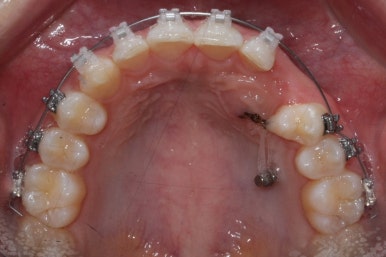

부산매복치아교정 키다리아저씨치과에서 소수술을 마친 모습입니다.

우선 남아있던 유치는 발치를 했고, 매복 송곳니에 장치를 붙인 후 잇몸 밖으로 체인 형식의 연장선만 빼놓았습니다. (두 개의 화살표 중 위쪽 화살표) 매복치아를 적절한 방향으로 요리조리 당겨줘야 하기 때문에 미니스크류를 이용했습니다. (두 개의 화살표 중 아래쪽 화살표)

수평으로 누워있었던 송곳니의 각도가 바로 잡힐 때까지는 계속 미니스크류만을 이용해서 당겨줍니다. 치아는 뼈속에서 헤엄치듯이 조금씩 방향을 잡아갑니다.

적절한 시기가 되면, 나머지 치아들을 가지런하게 할 준비를 합니다. 부산매복치아교정 키다리아저씨치과에서 이번에 사용한 장치는 클리피씨 입니다.

점점 송곳니가 모습을 드러내기 시작합니다.

치아가 위치, 방향을 바꿀 때마다 치아를 당겨주는 방향과 힘도 적절하게 조절을 해줘야 합니다.

매우 섬세한 작업이 요구됩니다.